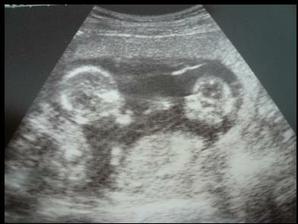

Naše kinderka

Dňa 24.8.2009 o 9.15 sa nám sekciou narodili naše krásne dvojičky Vanesska 2280 g a Larinka 2990 g. Robia nám veľkú radosť a moc ich ľúbime...